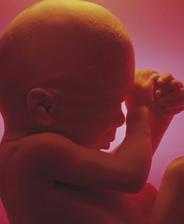

Miminko..(těhotenství a jeho průběh aneb co všechno můžeme vědět)

Jak asi víte, těhotenství je členěné na tři časové úseky, kterým říkáme trimestry – každý z nich trvá tři měsíce. Každý z trimestrů je zcela specifický, probíhají v něm určité charakteristické změny, podstupuje se vyšetření a nesou s sebou jiné pocity a obavy nastávající maminky.

V okamžiku zjištění těhotenství se žena ocitá na prahu zhruba čtyřicetitýdenní cesty. Někomu se zdá, že tato doba uteče jako voda, jindy je to vnímáno jako nekonečný proces. Každé těhotenství je individuální. Pro zdárný průběh těhotenství je důležitá tělesná a duševní pohoda.